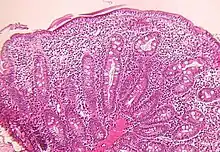

Small bowel

Microscopic examination of a biopsy of the small bowel in these patients shows villous atrophy with low or no mononuclear cell infiltration of the lamina propria nor specific abnormalities involving the epithelium. The amount of villous atrophy does not explain the severity of the diarrhea.